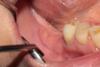

вот, кстати, сняла швы:

Очень редко, если трансп плохо адаптируется:

у меня такая картина, если трансплантат отваливается